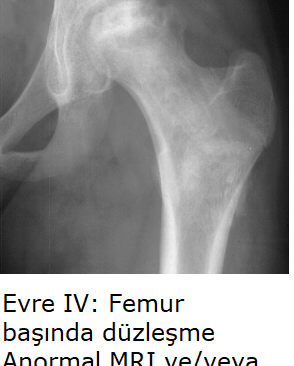

Evre IV: Eklem aralığında daralma, ileri osteoartrit. Terminal safha.

C. Kırmızı Bölge (Post-Collapse / Mekanik İflas - Evre III/IV)

Profil: Crescent Sign (+), çökme gerçekleşmiş. Tutulum >%50.

Strateji (Rekonstrüktif): Genç hastalarda yükü kaydırmak için Osteotomi; ileri evrede Total Kalça Artroplastisi (THA - Kalça Protezi). Cerrahi sonrası diğer kalçayı korumak için profilaktik protokol başlatılır.